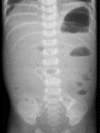

A four-day-old boy presented with persistent bilious vomiting, bloody stained stool, and mild abdominal distension. Transabdominal ultrasound demonstrated a round soft-tissue mass-like structure in the right upper quadrant. With color Doppler ultrasound, the whirlpool sign was observed. Abdominal radiograph showed nonspecific findings. Upper gastrointestinal series revealed upper gastrointestinal tract obstruction at the level of distal duodenum. The diagnosis of intestinal malrotation with midgut volvulus was established and the treated surgically. Intestinal malrotation is congenital abnormal positioning of the bowel loops within the peritoneal cavity resulting in abnormal shortening of mesenteric root that is predisposed to midgut volvulus. Neonates and infants with persistent bilious vomiting should undergo diagnostic workup and preferably ultrasound as the first step. With classic sonographic appearance of whirlpool sign, even further imaging investigations is often not needed, and the surgeon should be alerted to plan surgery.